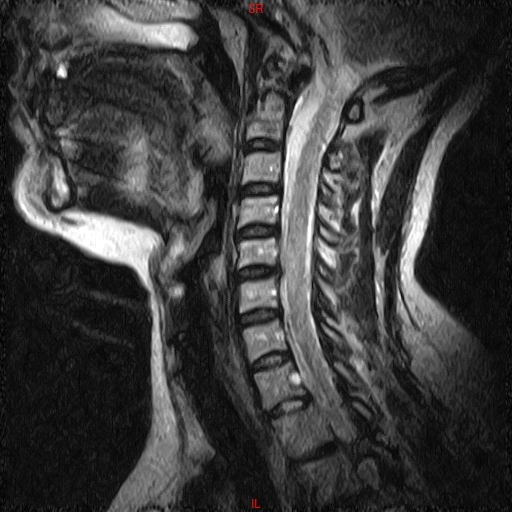

• Resonancia PATOLÓGICA DE C.CERVICAL -  SAG T2